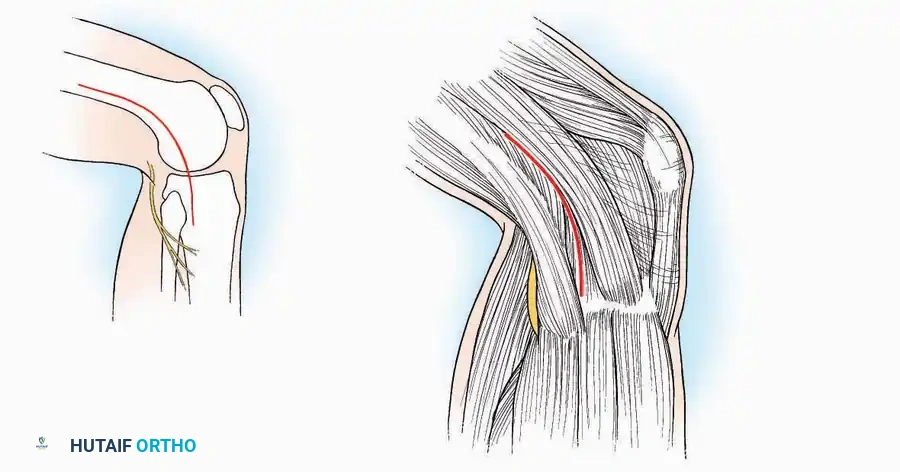

* Nerve Protection: The sural nerve crosses the proximal and distal limbs of this approach. It must be identified and protected within the anterior flap.

* Neurovascular Warning: Meticulously identify and protect the medial calcaneal nerve and the nerve to the abductor digiti minimi (first branch of the lateral plantar nerve), which are highly vulnerable during inferior retraction.

* Nerve Protection: Retract the skin edges carefully. Identify and protect the intermediate dorsal cutaneous branches of the superficial peroneal nerve (SPN), which frequently cross the distal aspect of this incision.

* Superficial Dissection: Incise the superficial fascia. Identify and protect the superficial peroneal nerve branches laterally and the saphenous nerve medially.